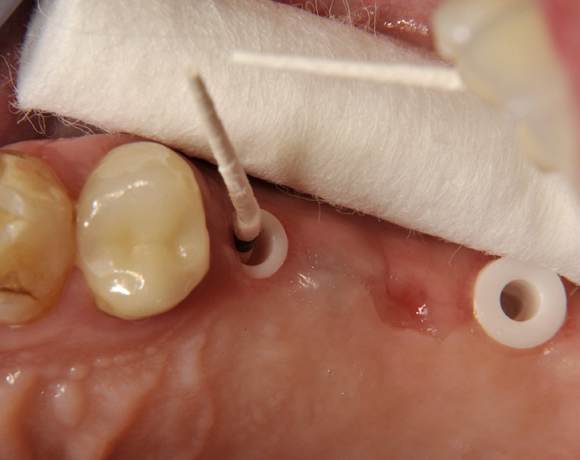

Im vorliegenden Patientenfall wurden für die Zähne 25 und 27 jeweils ein Implantat gesetzt. Nachdem die Implantate eingeheilt waren, wurde 25 – 27 mit einer Brücke versorgt.

Der operative Teil